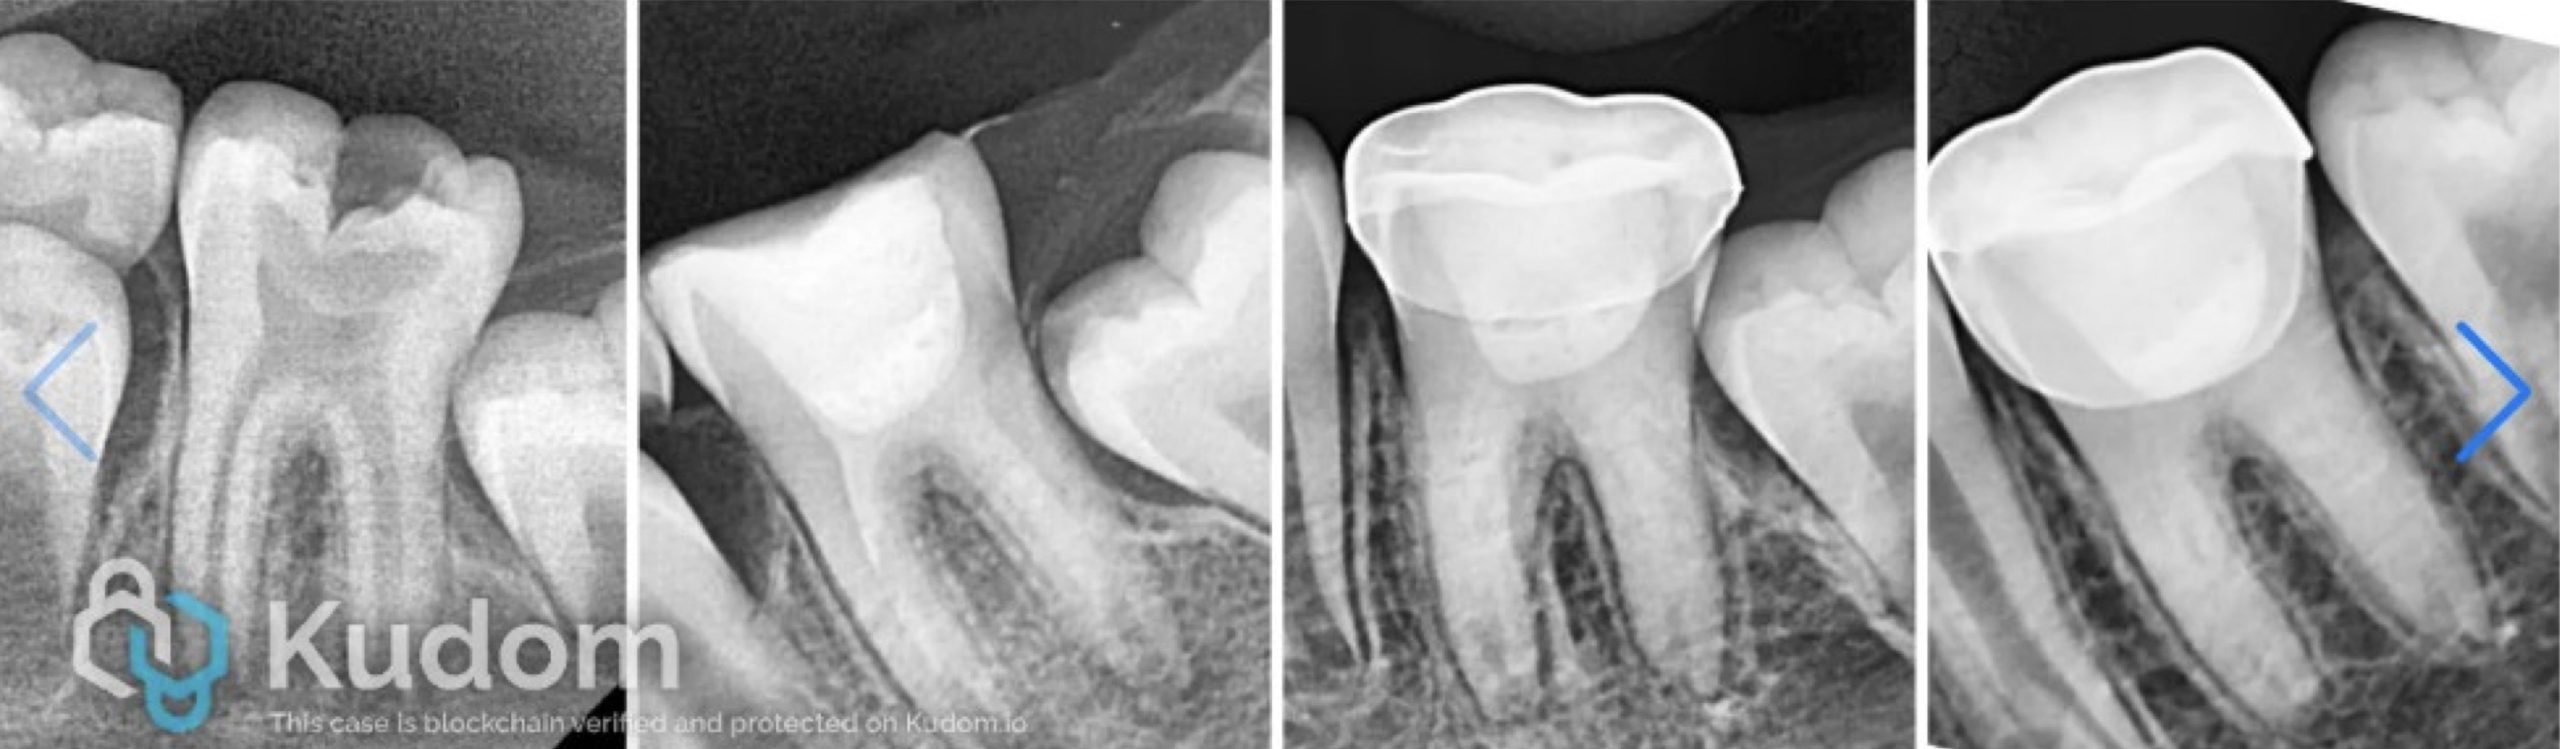

Root canal system is a very complex three-dimensional system. Although there are general rules about the anatomy, number of root/s or canal/s for each tooth, but we should expect everything. For that reason, we should have goon understanding, good reading of radiographs, good tools, and experience to deal with different scenarios